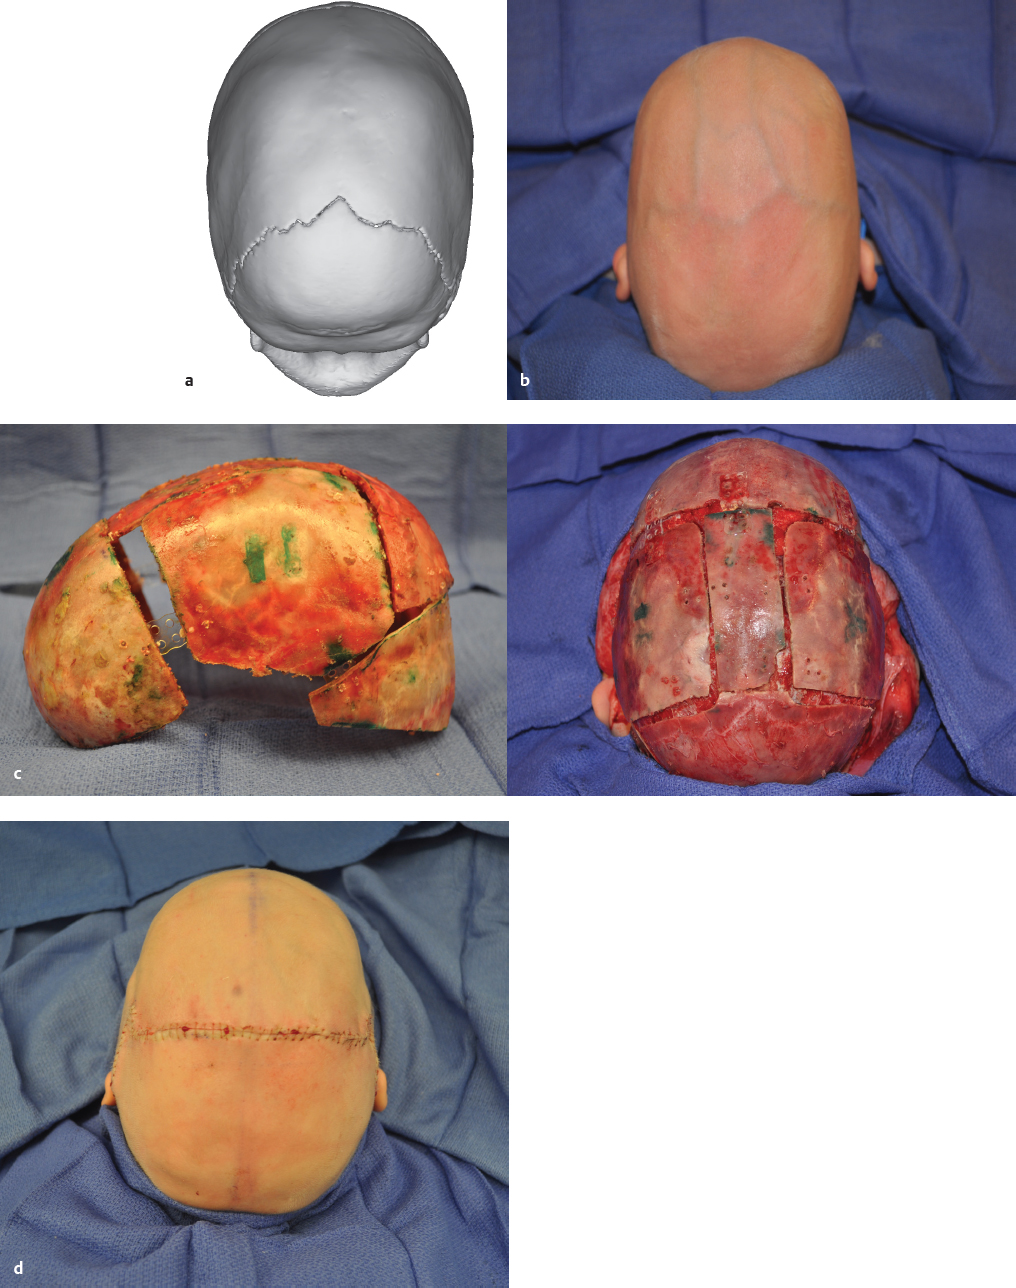

Craniomaxillofacial deformities present a range of abnormalities based on congenital conditions, trauma, and tumors. This chapter concentrates on congenital deformities, which present as a continuum from nonsynostotic deformations (posterior plagiocephaly), to single-suture synostosis, to multiple-suture craniosynostosis (craniofacial dysostosis) ( Fig. 66.1 and Table 66.1 ). Treatment of the craniosynostoses extends from conservative to multiple complex reconstructions, which may require many years; the central most basic advancement is the fronto-orbital advancement and frontal bone remodeling ( Fig. 66.2 ).

Craniosynostosis or premature fusion of the coronal, sagittal, metopic, or lambdoidal sutures ( Fig. 66.1 ) may be primary or secondary to known teratogens, metabolic disorders, hematologic disorders, or malformations such as microcephaly. 18 Craniosynostosis can also be found when patients are overshunted and sutures subsequently override and fuse. 19 , 20 The condition may be “isolated,” involving a single suture, or “complex,” involving multiple sutures. 17 , 21 Approximately 100 different forms have been described. Pathophysiology may be heterogeneous because phenotypes do not always associate with specific mutations. 21 , 22 Phenotypes have been classified as nonsyndromic and syndromic; the latter have been linked to several chromosomes. 18 , 23 For patients to carry a diagnosis of syndromic craniosynostosis, they must present with additional anomalies that exist in an embryologically distinct location from the craniofacial skeleton.

Most cases of craniosynostosis are single suture nonsyndromic patients. The developing calvarial ossifies in an intramembranous pattern whereby bone develops directly from mesenchymal precursor cells in a perpendicular direction from the cranial sutures. A complex interplay exists between the developing brain, dura, and pericranium that coordinates ossification. The dura maintains a strong osteogenic potential until early childhood. 24 Diagnosis of cranial suture synostosis is based on the knowledge of perpendicular growth from the suture. Once a suture is fused, growth will be restricted around the suture in a perpendicular fashion with compensatory changes along the open sutures; this results in welldefined cranial morphologies ( Fig. 66.1 ).

The evaluation of full-term infants with potentially misshapen heads is straightforward. 50 A long, narrow, boat-shaped head termed scaphocephaly indicates sagittal synostosis ( Fig. 66.3 ). The cephalic index is a common measure of the degree of severity in scaphocephaly. The normal cephalic index is ∼80, as measured by the cranial width over the cranial length multiplied by 100. Indexes under 71 are indicative of scaphocephaly. A top view of the typical distortion of sagittal synostosis is shown in Fig. 66.5a .

Unilateral and bilateral coronal synostoses are recognized by their forehead deformities ( Fig. 66.4 ). These are termed the anterior plagiocephalies. Bilateral coronal sysnostosis cases present with a symmetric short and tall skull termed turribrachycephaly. Cranial index in these patients will be elevated >82 to 85; patients with an index greater than 85 have severe brachycephaly. Unilateral coronal sysnostosis cases are often the most difficult to treat and present with varying degrees of frontofacial dysmorphology including an ipsilateral retruded brow and raised eyebrow. Growth arrest along the squamosal suture line resulting in the characteristic radiograph finding of a harlequin deformity is diagnostic. Often the contralateral forehead will be significantly bossed, accentuating the frontofacial asymmetry.

Metopic synostosis presents with the characteristic trigonocephaly shaped forehead. Examination reveals a prominent metopic suture with narrowing and elongation of the skull in the posterior direction. The forehead may be noted to be “keel” shaped, and the bitemporal distance in these patients is decreased; in severe cases, the patient may be hypoteloric ( Fig. 66.6 ).

Lambdoidal suture synostosis comprises the lowest frequency of synostosis cases. These are termed posterior plagiocephaly and are notable for occipital flatness along the effected suture with a mastoid bulge in addition to a posterior and inferiorly displaced ipsilateral ear. The ear position helps to differentiate posterior plagiocephaly from deformational or positional plagiocephaly.